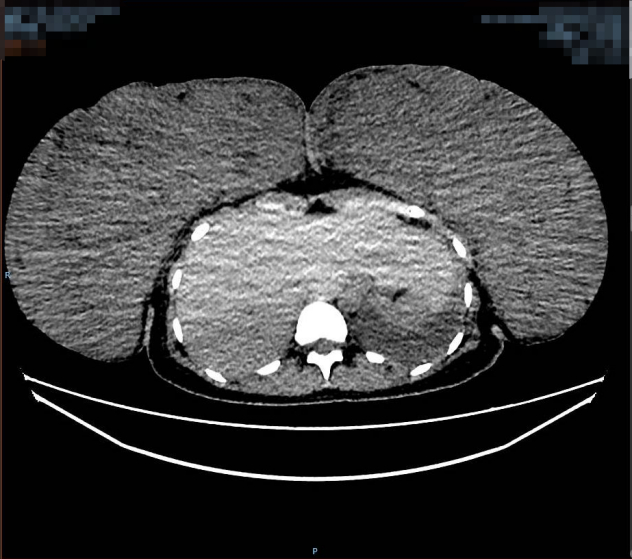

该患者胸部增强CT术前(左图)术后(右图)对比图,其中术前大小约:267mm×100mm×293mm(左),125mm×270mm×340mm(右)